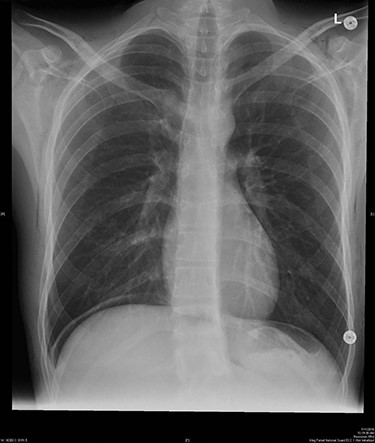

The patient was kept under observation for 24 hours. ABG was performed revealing the following values: pH 7.44; PaCO2 35.9 mmHg; HCO3 24.1 mmol/l and PaO2 90.8 mmHg. The final pre-discharge radiography showed improvement in the SE (Fig. 2) which has been resolved spontaneously.

Final pre-discharged x-ray showed improvement of the SE compared to the intra-operative x-ray.